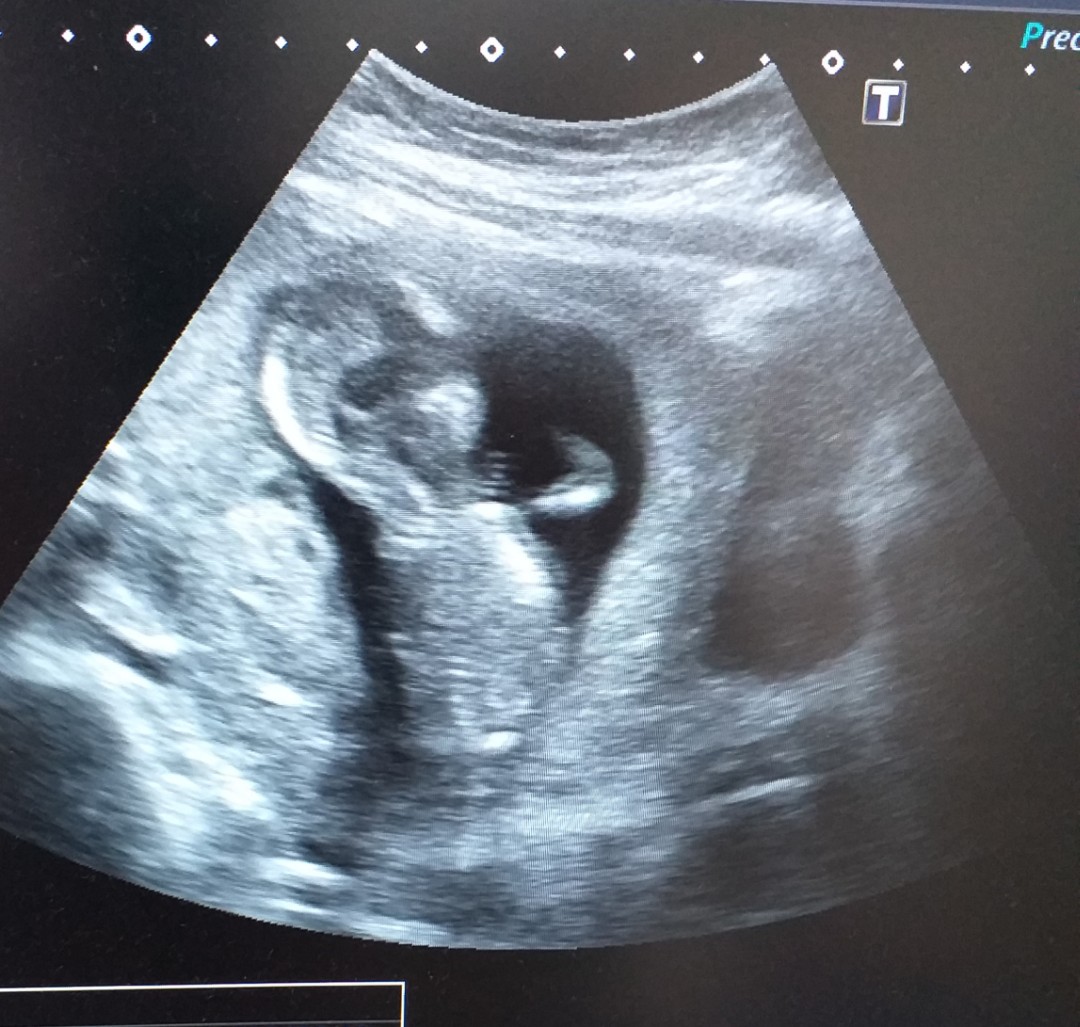

15w1dค่ะ💕😆😂